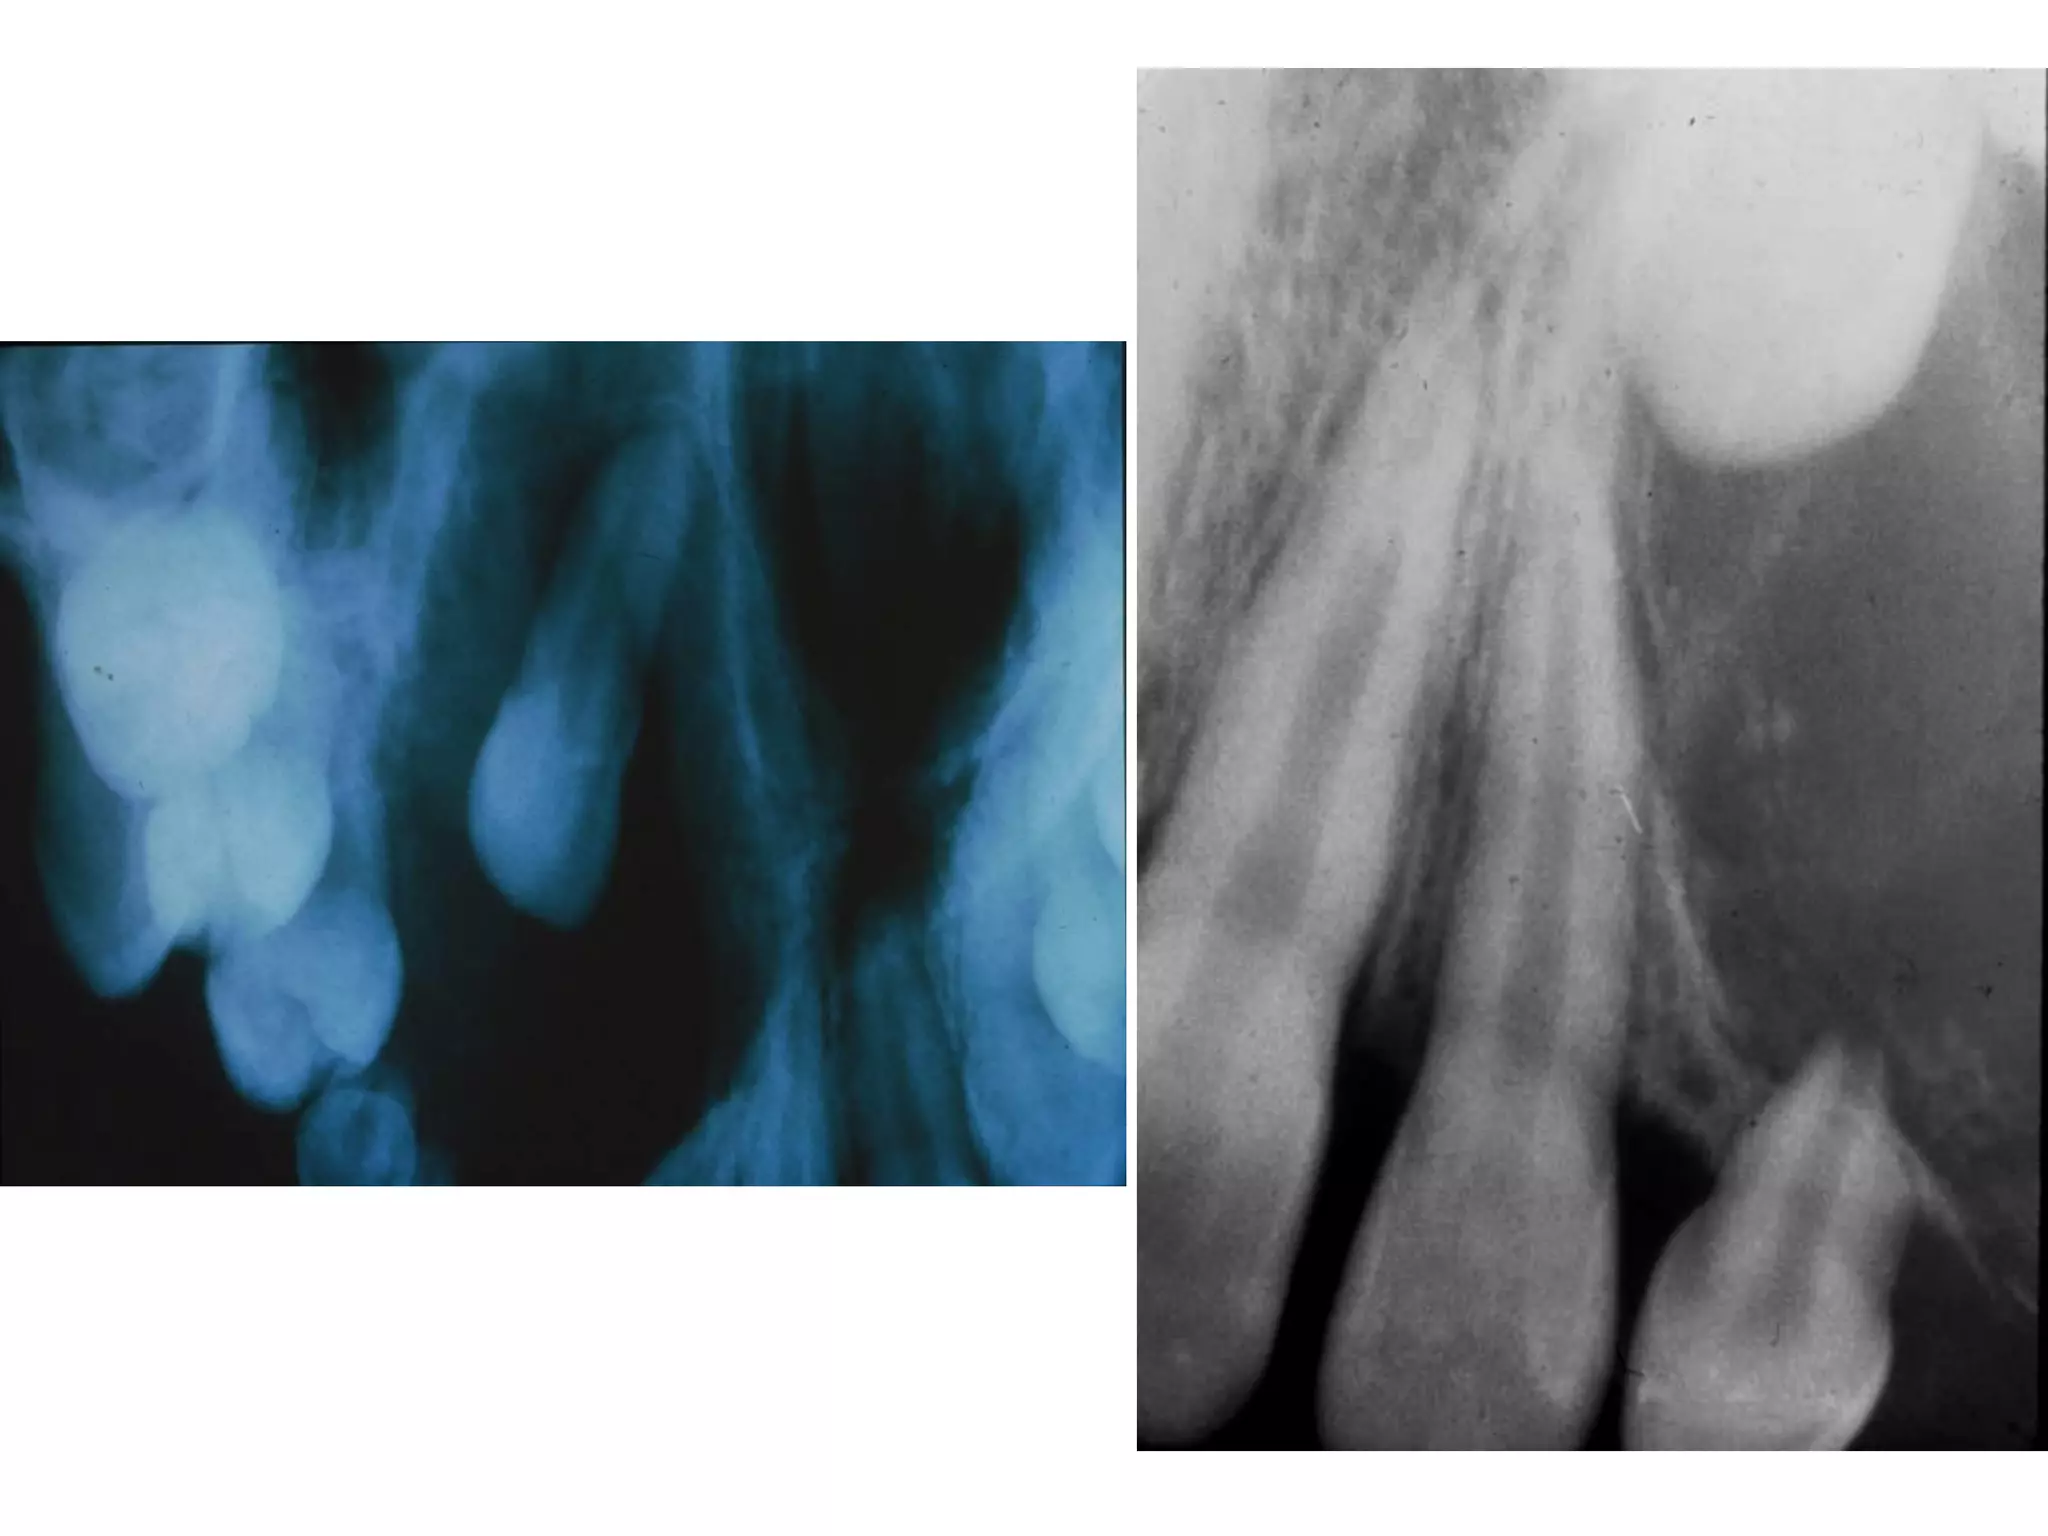

X quang: toån thöông thaáu quang thöôøng coù ranh giôùi roõ;

coù theå moät hoác hay nhieàu hoác (boït xaø phoøng, toå ong);

thænh thoaûng u coù ranh giôùi khoâng roõ, bôø nham nhôû.

X quang: thaáu quang quanh thaân raêng ngaàm (ña soá laø

RCL3 döôùi).

X quang:

Toån thöông thaáu quang quanh thaân raêng, coù theå

coù caûn quang beân trong khoái thaáu quang

(“boâng tuyeát”).

X quang: thöôøng laø 1 hoác thaáu quang roõ hoaëc

hieám hôn laø nhieàu hoác thaáu quang vôùi caùc

chaát canxi hoùa caûn quang. Do ñoù coù theå cho

hình aûnh hoãn hôïp vöøa thaáu quang vöøa caûn

quang.